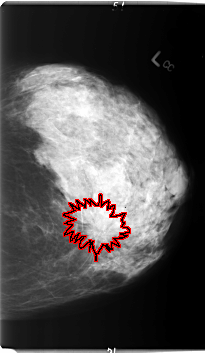

B_3006_1.LEFT_CC

LEFT_CC LINES 5992 PIXELS_PER_LINE 3480 BITS_PER_PIXEL 12 RESOLUTION 50 OVERLAY

FILE: B_3006_1.LEFT_CC.OVERLAY

TOTAL_ABNORMALITIES 1

ABNORMALITY 1

LESION_TYPE CALCIFICATION TYPE PLEOMORPHIC DISTRIBUTION CLUSTERED

LESION_TYPE MASS SHAPE IRREGULAR-ARCHITECTURAL_DISTORTION MARGINS ILL_DEFINED-SPICULATED

ASSESSMENT 5

SUBTLETY 3

PATHOLOGY MALIGNANT

TOTAL_OUTLINES 1

BOUNDARY